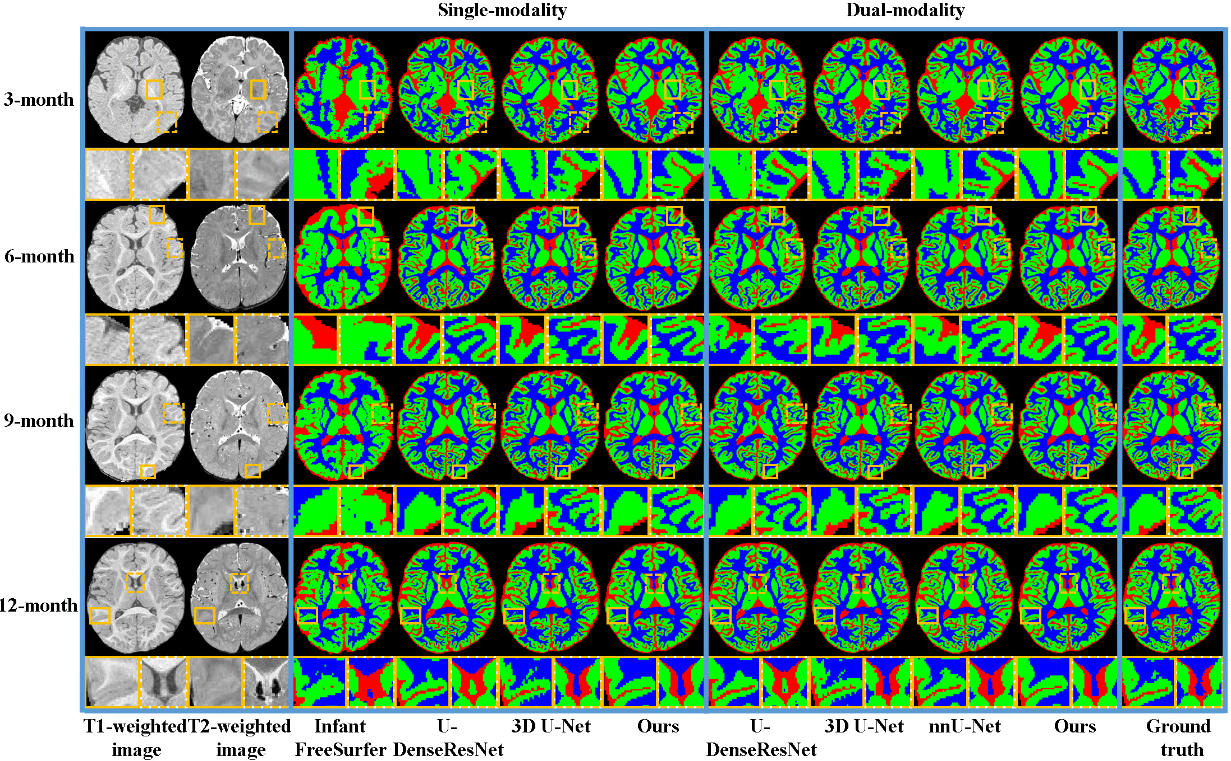

4、探索0-6岁儿童脑图像的分割算法

大脑结构的自动分割在研究纵向脑发育中具有重要作用,不同时间点的脑图像需要多个模型进行分割,给评估脑发育趋势带来一定偏差。为此,本研究提出了一种统一分割模型,结合纵向脑MRI作为引导的分割-配准框架,用于分割0-6岁儿童脑图像。该模型可以适用于单模态或双模态的输入信息,扩大了其在临床应用中的场景。提出的方法在目前最大的纵向脑数据集上进行了验证,并实现了最佳性能。这意味着它可以成功集成到儿童脑图像分析的流程中,并基于上海联影智能医疗科技有限公司的研究平台发布,以支持中国脑计划项目。

图2 脑组织分割的对比结果

相关研究成果以“Unified Model for Children’s Brain Image Segmentation with Co-Registration Framework Guided by Longitudinal MRI”为题发表于IEEE Journal of Biomedical and Health Informatics。九游体育(www.jiuyou.com)官方网站沈定刚课题组博士研究生滕琳为第一作者,九游体育(www.jiuyou.com)官方网站常任正教授沈定刚和特聘研究员石峰为共同通讯作者。九游体育(www.jiuyou.com)官方网站为第一完成单位,上海联影智能医疗科技有限公司为合作单位。